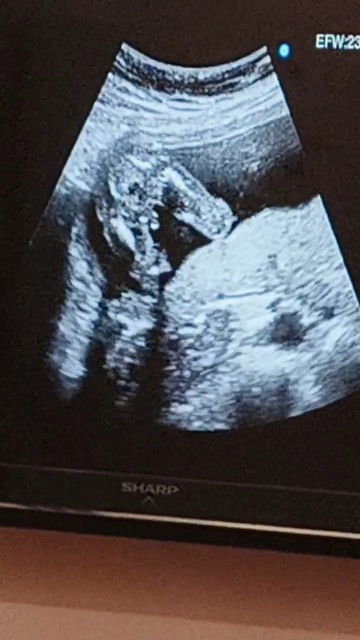

Hello po! ask ko lang po anong part po ba ito sa katawan ni baby.? saka nakikita nyo po ba kong ano na po gender ni baby? di po kase napaliwanag masyado ni OB akala po ata ayaw pa namen malaman gender ni baby po. salamat po sa sasagot🥰 #17weeks&4days #teamApril2025#AskingAsAMom #pregnancy #respectpost #17weeksand4dayspregnant